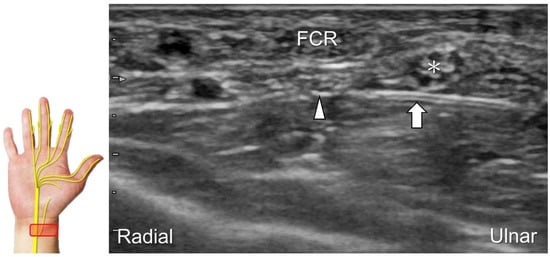

Scanning Technique

During scanning, the forearm is supinated with the transducer placed along the axial plane of the distal forearm. Moving the transducer more distally, the palmar ulnar cutaneous nerve can be seen as a single hypoechoic fascicle departing from the radial side of the main trunk near the bifurcating point for the dorsal ulnar cutaneous nerve (Figure 18A). It is crucial to apply light touch without compressing the adjacent vein, which can be used to highlight the nerve’s border.

Clinical Implication

The palmar ulnar cutaneous nerve has been associated with certain peripheral vascular disorders that can lead to arterial constriction and erythema over the hypothenar eminence [42]. The nerve may be persistently entrapped due to the presence of an accessory abductor digiti minimi muscle (Figure 18B) [42].